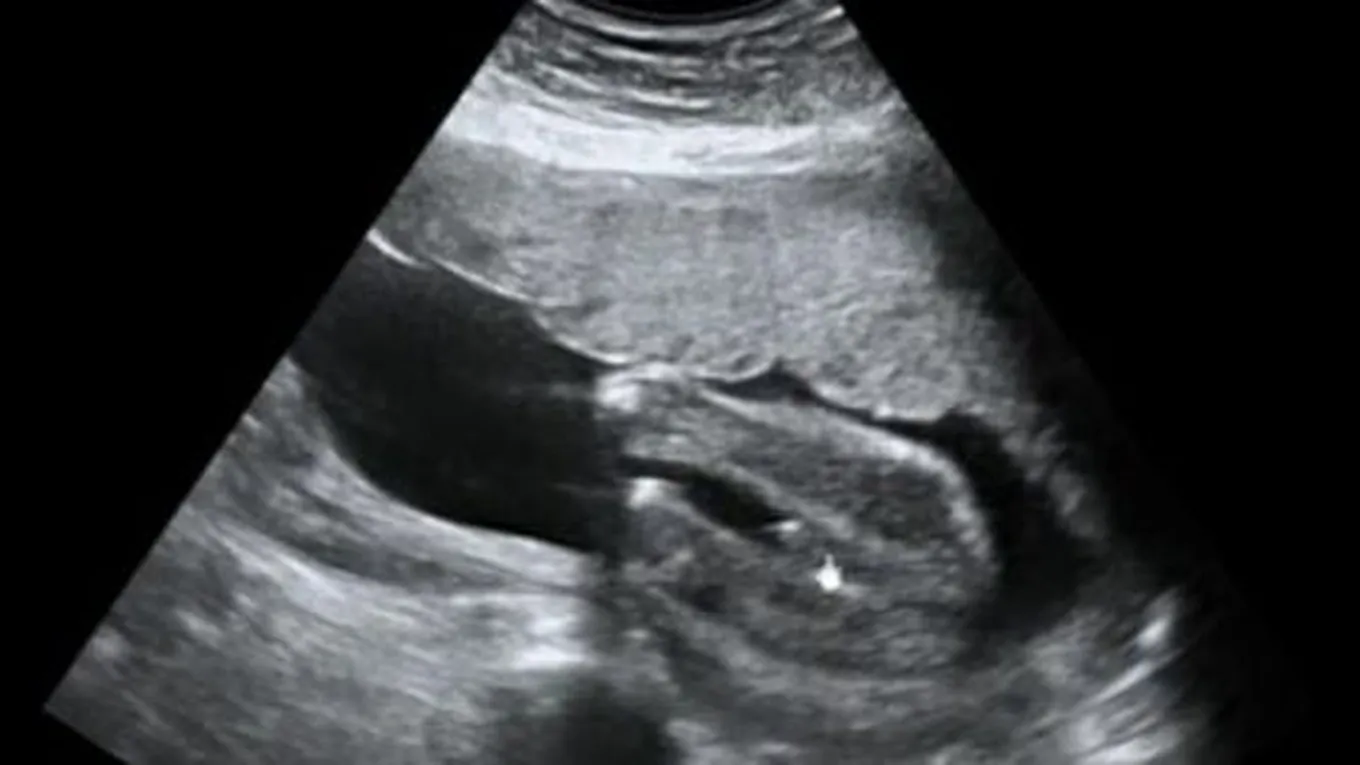

يُجري الاختصاصي مسحاً تفصيلياً للجنين عن طريق الموجات فوق الصوتية (بالإنجليزية: ultrasound)، وغالباً يتم إجراء هذا الفحص بين الأسبوع الثامن عشر والعشرين من الحمل، وخلال هذه الأسابيع تبلغ نسبة الدقة في تحديد جنس الجنين 99%، وينخفض معدل الدقة بشكل كبير قبل الأسبوع الرابع عشر من الحمل، حيث يتم في هذا الفحص قياس حجم الجنين، والتحقق من الأعضاء الرئيسية له، والتحقق من وضع المشيمة، وقياس مستوى السائل الأمنيوسي للتأكد أنه بالمستوى المطلوب، وفي هذه الفترة الزمنية من تطور الجنين يمكن للوالدين التعرف على نوع الجنين.[1]